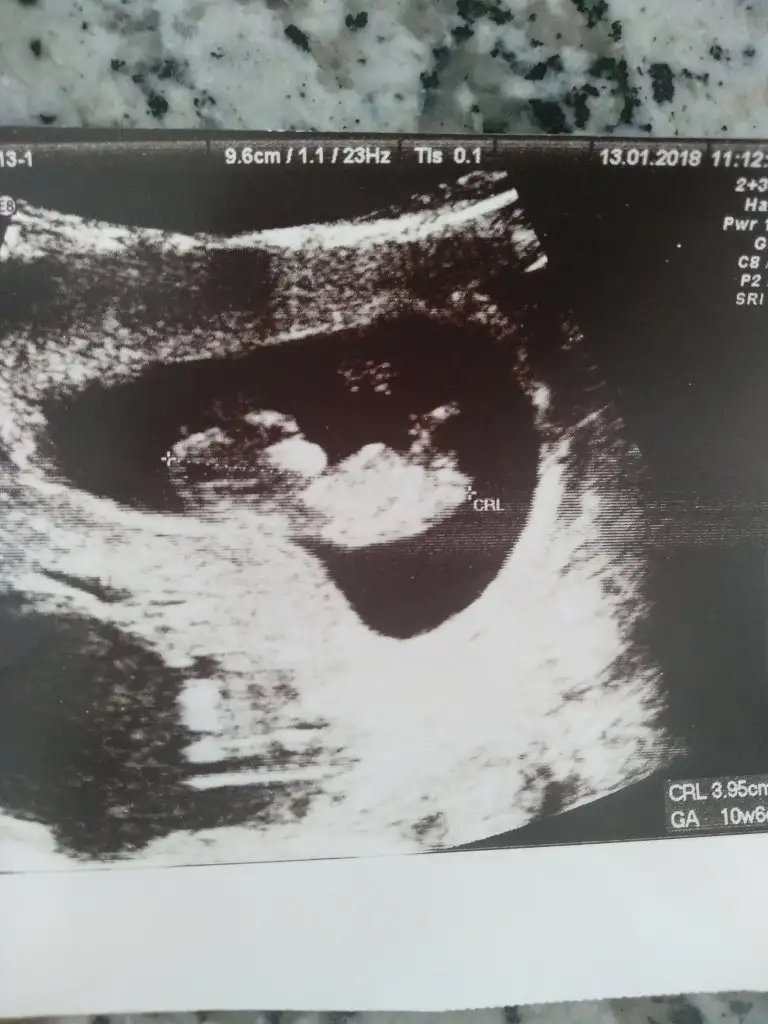

Muhittin Bacim ben ikili test icin 11+4 de falan gitmis olcakdm yani kan falan vermicem sadece ense kalinligi falan olculecek ayrintili ultrosnda tarihi doktor kendi verdi bebek en son önde gidiyordu ona dayanarakmi bu tarihi verdi bilmiorm ama senin ki gec olmuo mu 13.hafta